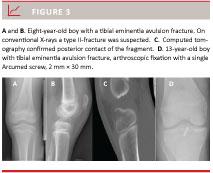

The patients’ symptoms were pain, swelling, a sensation of locking of the knee and limited range of motion [1, 7, 9, 14, 15, 18-30]. A proper clinical examination can only be done in universal anaesthesia [4, 17, 18, 22] where conventional tests can be used; a positive Lachman’s test [4, 9, 12, 15, 18, 22, 26, 28, 30-32], anterior drawer test [4, 9, 15, 26, 28, 31] and Pivot Shift [4, 29, 30]. Most studies used roentgenograms in three views (lateral, antero-posterior and tunnel view) to validate the clinical findings (Figure 3). Senekovic & Veselko found that diagnostics by X-ray was generally correct, but 28% of type III-fractures were classified as type IV when seen arthroscopically [33]. Some authors preferred to use magnetic resonance imaging (MRI) as supplemental diagnostic imaging [5, 20] to confirm the diagnosis and also to evaluate associated soft tissue injuries. Otherwise, arthroscopy [4, 9] was used as a diagnostic tool with or without subsequent surgical intervention although three authors abstained from arthroscopy and proceeded directly to fixation by arthrotomy or conservative treatment [8, 10, 17]. Iborra et al even discouraged the use of arthroscopy as a diagnostic tool [17].

In most cases, TEAF can be diagnosed with conventional X-rays. When in doubt, a CT should be performed if it can be done without delay to further evaluate if surgery is needed.